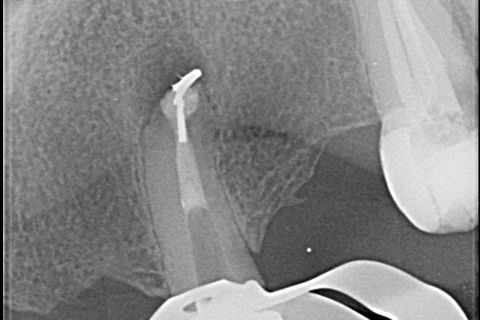

Expulsão do Cone de Prata

Raio X imediatamente após a cirurgia

A modelagem do canal radicular foi feita usando Lima Reciproc R25 (VDW - Alemanha) seguido por Lima Reciproc Azul RB50 (VDW - Alemanha). Durante o retratamento endodôntico, foi feita uma irrigação abundante com 2,5% de hipoclorito de sódio. Depois de várias tentativas para remover a parte remanescente do cone de prata, outra separação ocorreu (Figura 4). Parte do cone de prata foi removida do canal. No entanto, o outro fragmento não pôde ser removido.